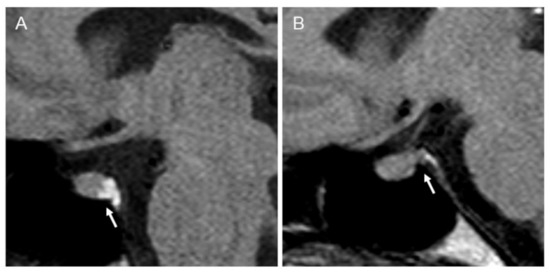

Plasma osmolality and plasma sodium increased after 3 h of fluid deprivation to 313 mOsm/L and 149 mmol/L, respectively. However, the extensive hypertonic dehydration elicited a prompt elevation of urine osmolality and diuresis contraction, without achieving a loss ≥5% of the initial body weight at the end of fluid deprivation testing, indicative of a partial clinical adFNDI phenotype [10,13]. The former diagnosis was confirmed by both normal basal pituitary function in extensive hormonal tests and evidence of normal gland morphology at neuroradiological assessment. However, in pre-enhanced T1-weighted MRI scans of the pituitary gland, the intrinsic hyperintense “bright signal” of the neurohypophysis was reduced (Figure 2) and this abnormal finding was regarded as compatible with the partial depletion and loss of function of vasopressinergic magnocellular secretory cells [15,16].

Figure 2.

Pre-enhanced T1-weighted magnetic resonance imaging (MRI) scan of the pituitary gland. Arrows indicate (A) a normal hyperintense “bright signal” of the neurohypophysis in an unaffected control subject; (B) a reduced “bright signal” in the index patient.